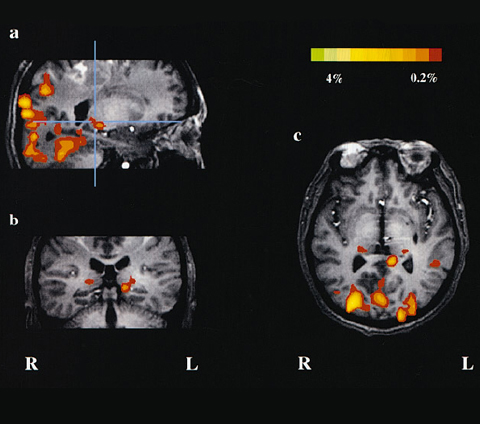

Se tienen convenios de colaboración para la realización de diversos estudios de gabinete con proveedores certificados para: